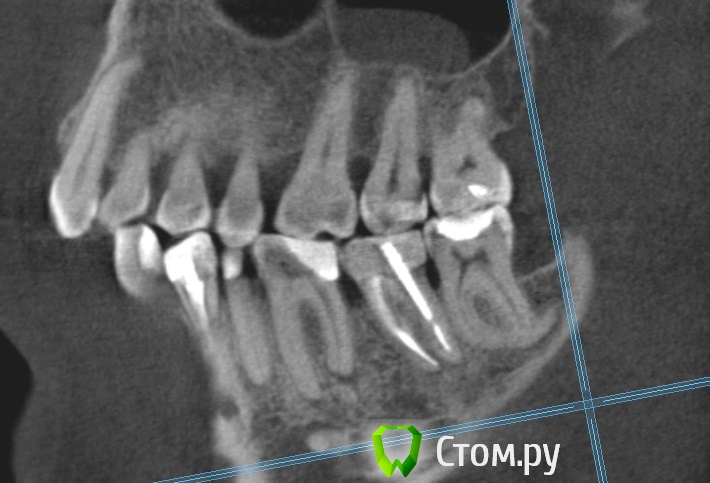

Dmitrich Опубликовано 30 сентября, 2014 Поделиться Опубликовано 30 сентября, 2014 Здравствуйте уважаемые форумчане. Вообщем такая у меня проблема, постараюсь описать менее сумбурно. Сначала я удалил 4.7 зуб из за кариеса корня. После этого примерно через неделю начались боли с другой стороны челюсти. Пришел на прием - мне по рентгену опредилили больной 3.7 (там был глубокий кариес и раза 3 переставляли пломбу на протяжении лет так 20) Его депульпировали, но боль не прошла. Сначала болело при накусывании (это нормально как я понимаю), потом просто стали ноющие боли. На месяц я уехал из города и боли были разной интенсивности. Обращался к двум разным стоматологам в отъезде - все гвоорили что это отстаточное явление после лечения. Постукивание по зубу чувствительно до сих пор. С тех пор уже 3 месяца - ноющие боли не проходят. Обращался в разные клиники, делал КТ месяц назад. Может не болеть дня 3-4 совсем, я уже обрадуюсь, на следующий день опять начинает тянуть. Утром всегда не болит, к обеду начинает. Чистили карман между 6 и 7. Результат улучшается на день-два. Ходил на прием к ортодонту, тот сказал нужно лечить 6й, состояние десен почти в норме, ко крайней мере острого воспаления нет. С КТ сделал скриншоты 6го и 7го, прикладываю. 6й зуб проверяли проводимость нерва аппаратом - результат ок )) Что мне все таки делать в данной ситуации? В клинике где лечил зуб говорят он вылечен нормально. Ссылка на комментарий

M@estro Опубликовано 30 сентября, 2014 Поделиться Опубликовано 30 сентября, 2014 Проблема в 3.6 Ссылка на комментарий

Korel Опубликовано 30 сентября, 2014 Поделиться Опубликовано 30 сентября, 2014 Проблема в 3.6 И (или) в 35 Ссылка на комментарий

Паращук Роман Опубликовано 30 сентября, 2014 Поделиться Опубликовано 30 сентября, 2014 (изменено) Или 3.6,2.7. Возможна трещина в 3.7 Изменено 30 сентября, 2014 пользователем Паращук Роман Ссылка на комментарий

Dmitrich Опубликовано 30 сентября, 2014 Автор Поделиться Опубликовано 30 сентября, 2014 Спасибо всем за советы. 2.7 сделал с месяц назад, не помогло. 3.6 получается делать точно? Странно вроде относительно недавно (года 2 назад) менял там пломбу из за того, что откололся край - вообще никаких проблем не было. Нерв проверяли - жив. То что на верхушках корня там - три месяца назад было тоже самое. А вот с трещиной вы напугали. Смотрели эту КТ несколько раз несколько стоматологов, трещину никто не увидел. Она же вроде сильно должна болеть? Ссылка на комментарий